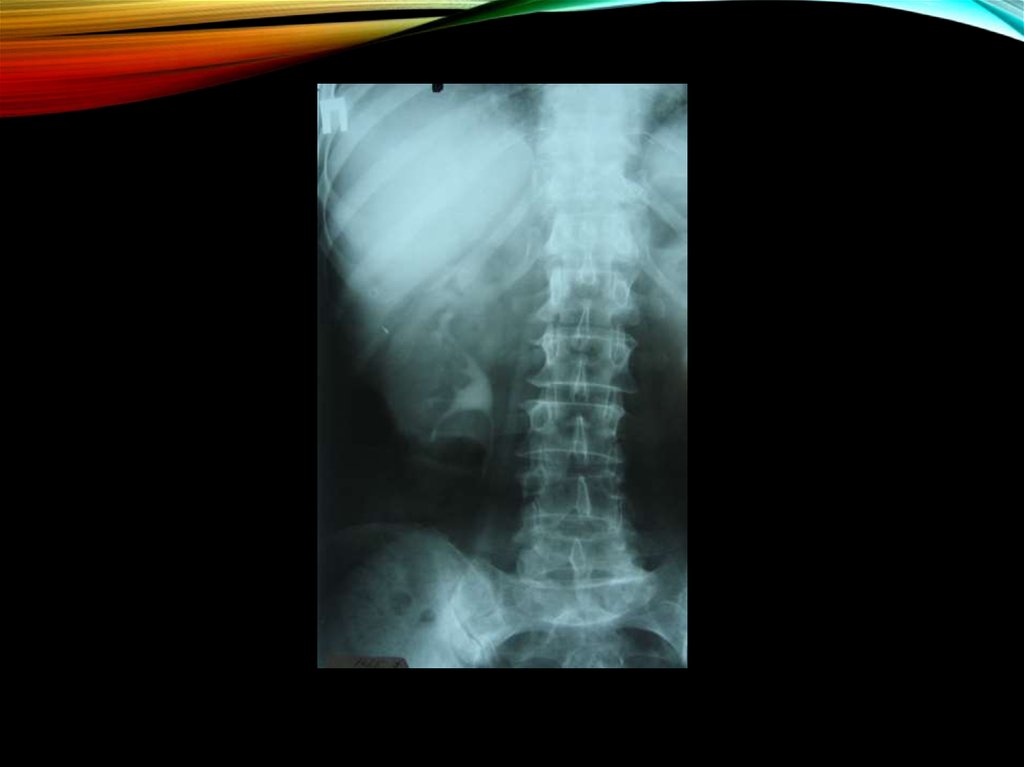

14. Изменения рентгенологической картины:

ИЗМЕНЕНИЯ

РЕНТГЕНОЛОГИЧЕСКОЙ

• увеличение в объеме пораженной почки

КАРТИНЫ:

• не контрастируются мочевыводящие пути на

пораженной стороне

• отсутствует контур поясничной мышцы

• при ретроградной пиелографии - сдавление чашечки и

лоханки, ампутация одной или нескольких чашечек